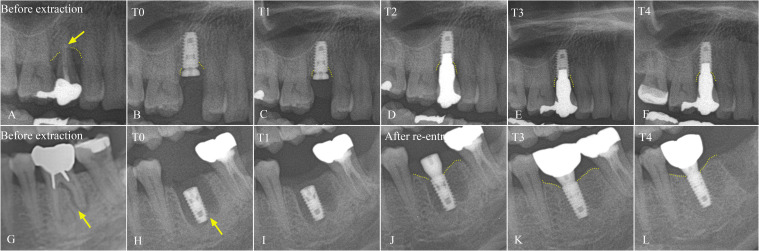

Methods: Between 2009 and 2018, a single surgeon at Seoul National University Dental Hospital in Seoul, Korea, immediately inserted 49 dental implants with tapered bone-level design after extraction, in a total of 34 patients. The clinical outcomes were collected and evaluated, focusing on location of implant placement and marginal bone loss (MBL), with consideration of other parameters such as implant diameter and length.

Results: Of 49 immediately installed Luna® (Shinhung Co., Seoul, Korea) dental implants, 23 were placed in the mandible, and 26 were set in the maxilla. The mean age of patients at the time of installation was 65.91 years, ranging from 40 to 86 years. The average follow-up period was 7.43 years, with a range of 5 to 14 years. After a 5-year retrospective evaluation of tapered, sand-blasted, and acid-etched internal submerged dental implants for immediate implant placement, the cumulative survival rate was 93.88%, with 100% survival rate in the mandible and premolar region of both the maxilla and mandible.